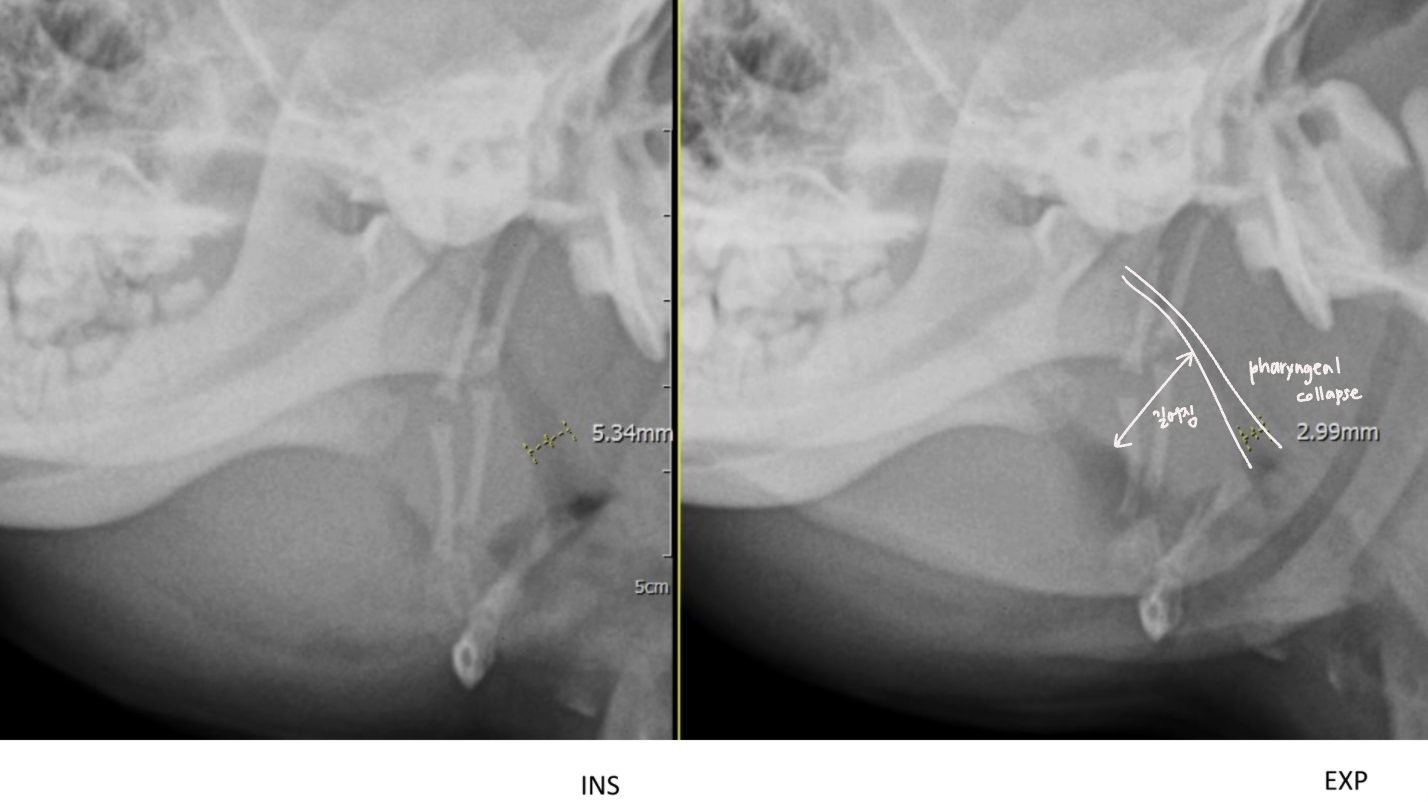

| Pharyngeal collapse : ํธ๊ธฐ ๋ ์ข์์ง - ์ฆ์์ ํก๊ธฐ์์ ๋ ์ฌํจ (ํก๊ธฐ์ฑ ํธํก๊ณค๋) ![]() ![]() |

| Hiatal hernia (์ ํํ) : ์๊ฐ ํ๊ฐ์ผ๋ก ๋น ์ง Gastro-esophageal reflux (GERD) ![]() |